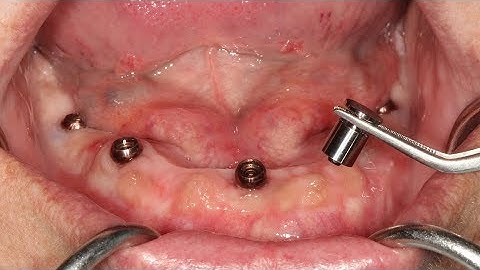

Clinical demonstration Introducing the Zest LOCATOR F Tx Fixed Attachment System and an Immedia